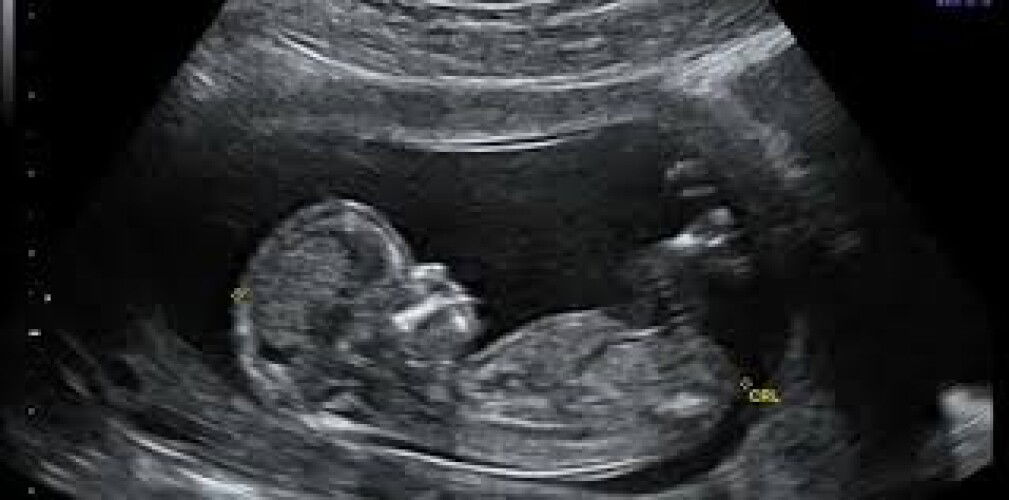

Berapa kerap kita boleh buat ultra sound?